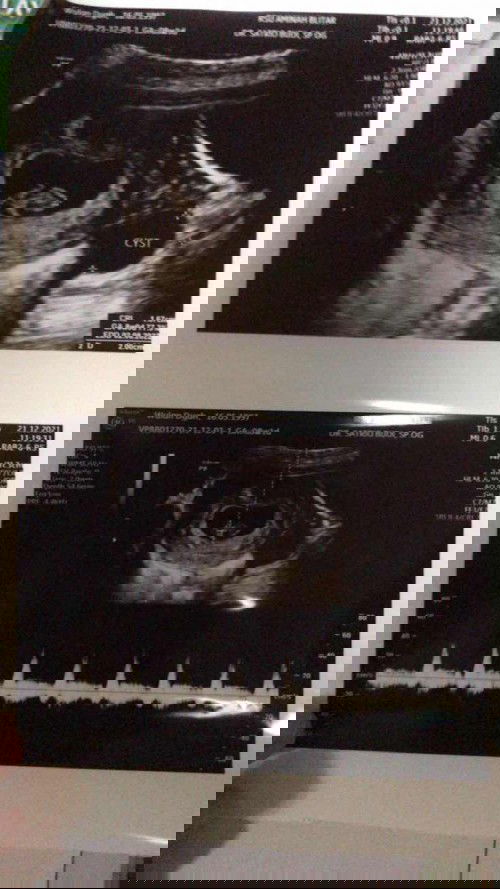

Bun mau nanya tentang kista di awal kehamilan

Saya sedang mengandung 8w5d, kemarin saya usg dan hasilnya bagus karena debay nya tumbuh normal dan detak jantung juga sdh terlihat. Namun, ada kista sebesar 2cm di ovarium kanan saya. Kata dr, hal ini masih umum terjadi di awal kehamilan karena biasanya akan menghilang dengan sendirinya. Namun akan tetap dipantau dalam sebulan ini. #ingintahu apakah ada kasus serupa yg dialami bunda lain? #firstbaby saya was was bun, meski dr bilang semua akan baik2 saja. #pleasehelp